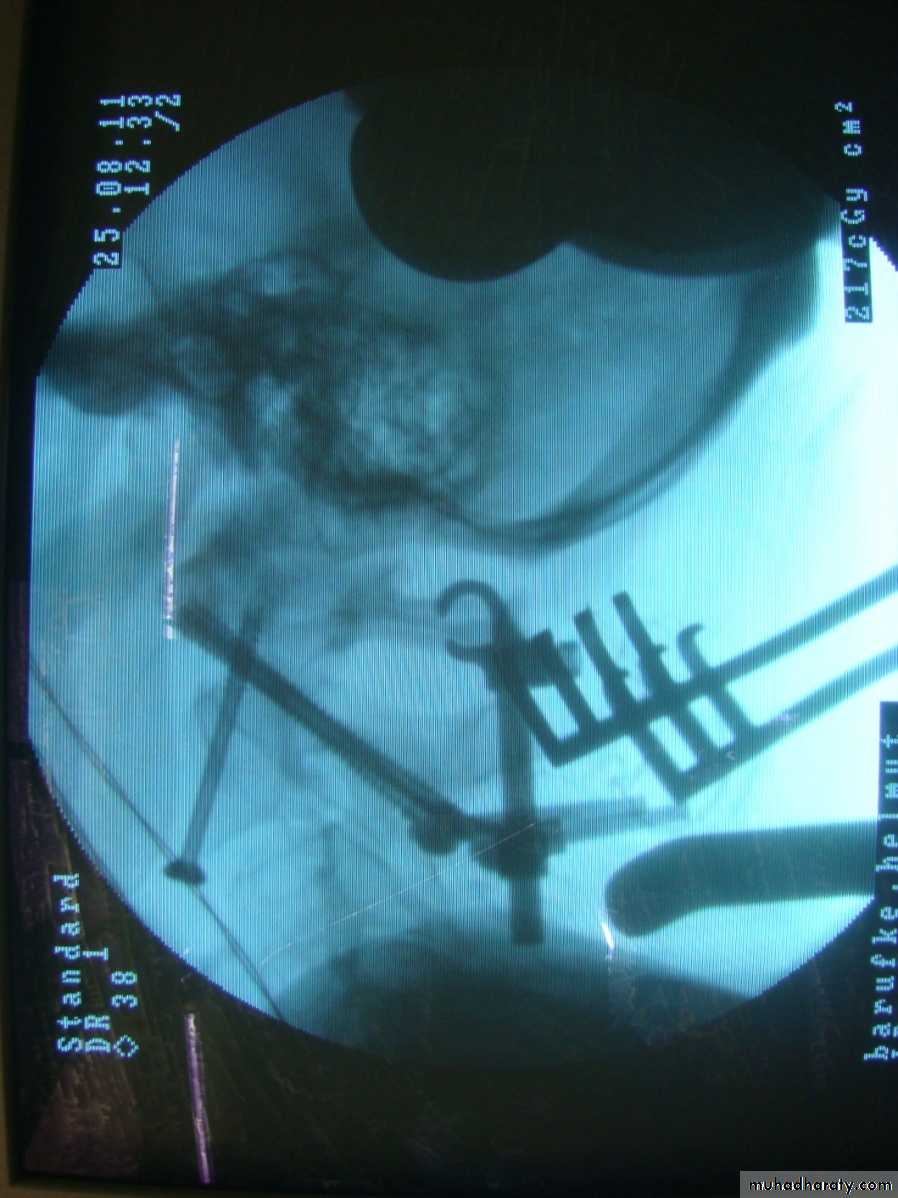

Type I # need immobilization in a rigid collar until discomfort subside.Type II # If undisplaced need halo-vest .Displaced # need reduction by traction &then held by either operative fixation or by halo-vest immobilization.

Type III # If undisplaced need halo-vest .Displaced # need reduction by traction then held by halo-vest immobilization.